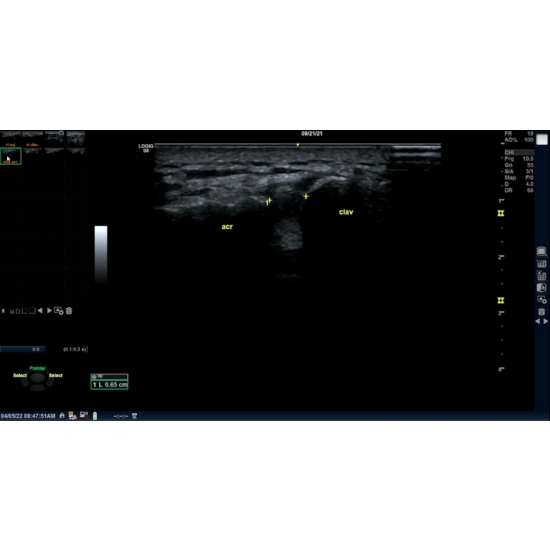

| Persistent Right Shoulder Pain - Page #3 | |||

Other Studies: |